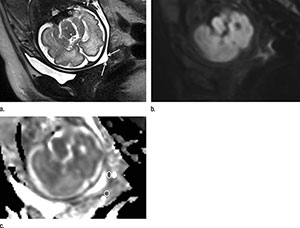

Cervical subglandular apparent diffusion coefficient (ADC) at MRI is associated with impending preterm birth in patients with a short sonographic cervix, according to new research published online in the journal, Radiology.

Gabriele Masselli, M.D., from Umberto I Hospital Sapienza University in Rome, Italy, and colleagues used pelvic 1.5-T MRI to study 30 pregnant women who had a sonographically short cervix. ADC values of the subglandular and stromal cervix, and the difference between both, were correlated to the interval to delivery.

Eight (27 percent) of the 30 patients delivered within six or seven days after MRI, and 22 (73 percent) of them delivered between 18 and 89 days after imaging. Overall, 19 (63 percent) of the patients experienced preterm delivery after less than 32 weeks of gestation.

“Our results indicate that a high ADC recorded at the level of the subglandular area of the cervix is associated with imminent delivery in asymptomatic patients who have a short cervix. This can be particularly useful in the acute care of patients who have a sonographically short cervix and positive fetal fibronectin test results in the early third trimester of pregnancy,” the authors write.